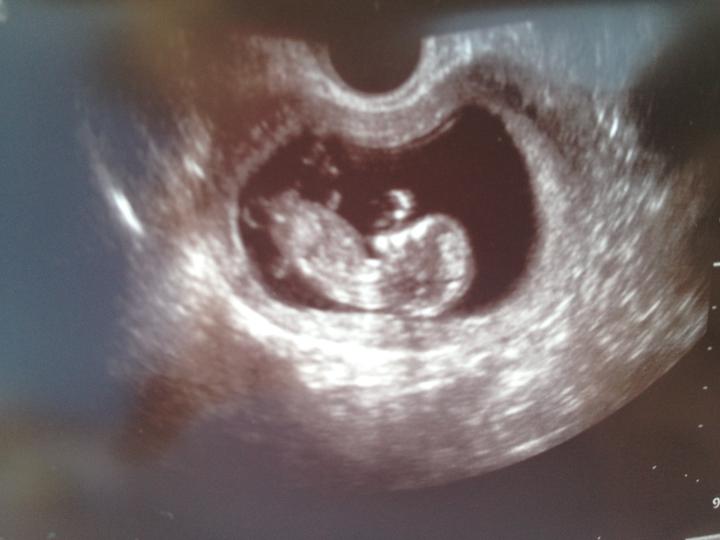

nase malinke ma uz 25 cm a 380 gramov.bol strasne zlatucky;)

Takze to bude chlapcek.Mathiasko:Dstraaaaaaaaaaaasne sa tesime:D